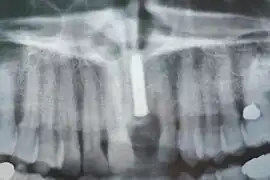

Prothèse totales fixes sur implants

Elles ont en règle réalisables sur six implants (selon des modalités bien précises pour l'observation desquelles le poseur d'implant doit avoir les qualifications requises). Selon la récession osseuse du patient à la suite de la perte de ses dents, on réalisera une prothèse sans ou avec fausse gencive. Moins coûteuses que les bridges, ces prothèses sont moins longues à réaliser. Rien n'empêche cependant le patient de faire remplacer sa prothèse résine par une prothèse céramique après une période d'observation de deux ans.

Radiographie des six implants

Contrôle de la cicatrisation à une semaine de l'intervention